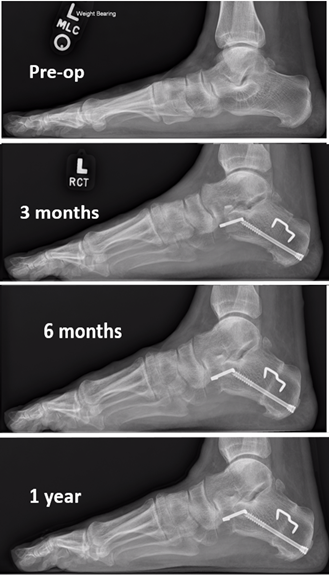

The Cotton Osteotomy In Flexible Flatfoot Correction

The Cotton Osteotomy in Flexible Flatfoot Correction www.hmpgloballearningnetwork.com

Flatfoot Surgical Correction | Flatfoot Surgery Procedure & Recovery

Flatfoot Surgical Correction | Flatfoot Surgery Procedure & Recovery www.footcaremd.org

flatfoot correction surgical ray foot views